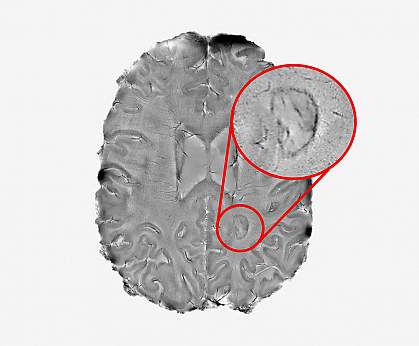

The immune system’s attack on the nervous system produces lesions that appear as spots on MRI scans of a patient’s brain. While some lesions heal, completely or partially, others remain chronically inflamed. Chronically inflamed lesions have a dark outer rim surrounding them on MRI scans and appear to actively expand for many years. These dark rims accumulate brain immune cells called microglia, which can sustain low-grade, or “smoldering,” inflammation.

Most of the study participants (56%) had at least one chronic active lesion—including those who were receiving the most current treatment options. The researchers classified the patient results into three groups: no rims (84 people); one to three rims (66 people); and four or more rims (42 people).

Patients with multiple chronic active lesions showed a more aggressive form of MS. Those with four or more rim lesions were 1.6 times more likely to have MS that progressed compared with those without any rim lesions. They were also more likely to experience physical and cognitive disabilities at a younger age.

“We found that it is possible to use brain scans to detect which patients are highly susceptible to the more aggressive forms of multiple sclerosis. The more chronic active lesions a patient has, the greater the chances they will experience this type of MS,” Absinta says. “We hope these results will help test the effectiveness of new therapies for this form of MS and reduce the suffering patients experience.”